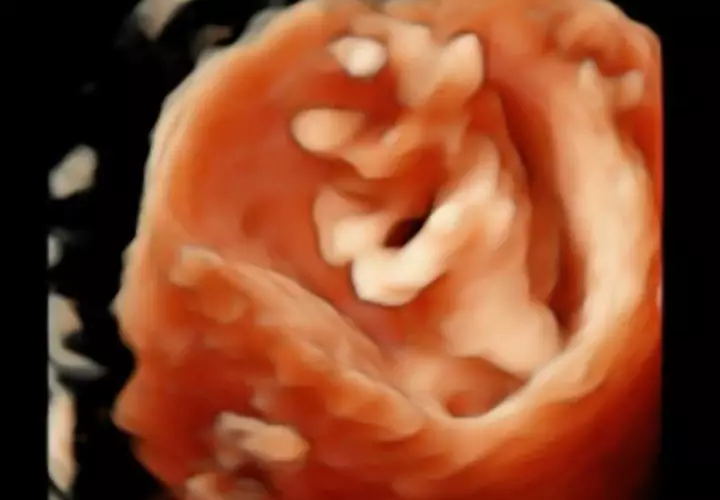

6. Audi pun membagikan cerita dan beberapa foto dalam pemeriksaan kandungannya di usia kehamilan 11 minggu.

foto: Instagram/@audimarissa

7. Aktris cantik itu mengaku kerap menangis pada malam hari karena merasa terharu memiliki seorang bayi di dalam perutnya.